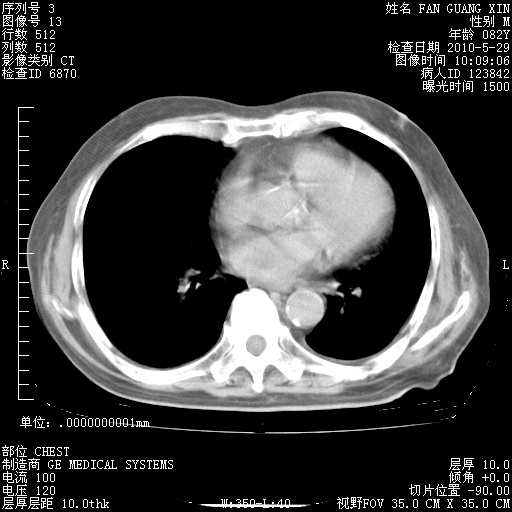

再治疗10天后的肺部CT

再治疗10天后的肺部CT 纵膈窗

阅读此次胸部CT,肺间质渗出性改变较入院时有吸收。目前从体温、白细胞、中性分叶明显增高,肯定存在细菌感染(发生医院感染哦,若无消化道及泌尿系统等感染的依据,肺部感染可能大)。若你院头孢哌酮舒巴坦钠耐药率较高,同意你的方案,若48小时体温仍高,可考虑使用碳青霉稀类抗菌药物,同时可予超声雾化、注意滴数时加大液体量。白蛋白33.30g/L较低哦,需加强营养等支持治疗。